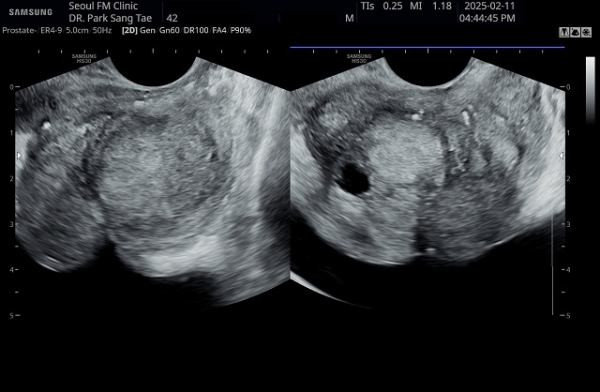

내원 당일 전립선의 정면 초음파 사진상 좌우 사정관 입구의 결석과 전립선의 이행구역에  비대해진 결절 그리고 우측 전립선 결절내 전립선 낭종이 관찰되며

방광쪽으로 커져 배뇨장애와 급박뇨가 심해 지고 있는 경직장 전립선 초음파 사진입니다.

This is a transrectal prostate ultrasound image taken on the day of the patient's first visit, showing stones at the openings of both ejaculatory ducts, an enlarged nodule in the transitional zone of the prostate, and a prostatic cyst within the right prostatic nodule. The prostate is enlarged toward the bladder, contributing to worsening voiding dysfunction and urgency.